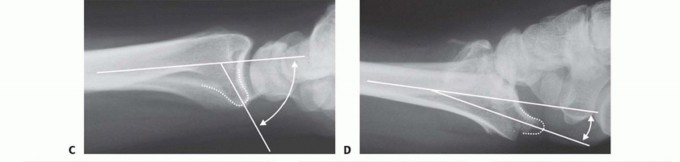

FIG 3 • Pathogenesis of dorsal radius fractures. A. Dorsal bending. B. Volar bending. C. Dorsal shear. D. Volar shear. E. Radial shear. F. Three-part articular. G. Comminuted articular. H. Carpal avulsion. I. High energy.

FIG 4 • A. Positioning for standard lateral radiography. B. Standard lateral radiograph. C. Positioning for 10-degree lateral radiography. D. Ten-degree lateral radiograph. Note the improved visualization of the articular surface of the base of the scaphoid facet and the entire lunate facet. Injuries from a high-energy mechanism present as complex comminuted fractures of the articular surface with extension into the radial/ulnar shaft ( FIG 3I).